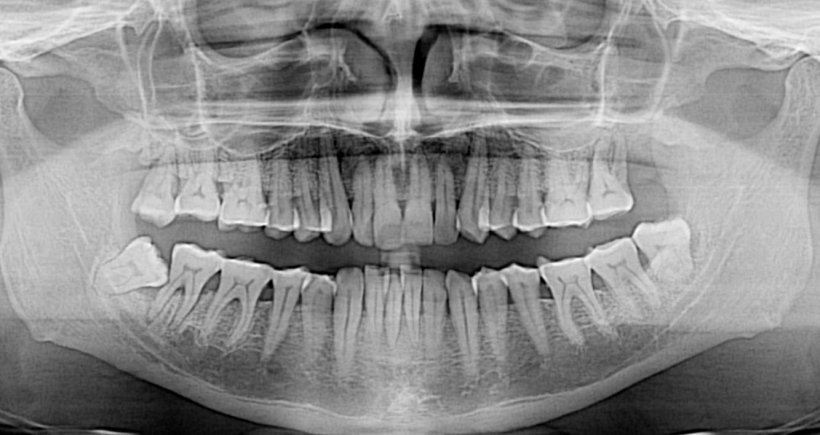

This futuristic discovery might be the end of expensive dental implants. Dentists have discovered how you grow your own teeth, in just nine weeks! A team from Columbia University led by Dr. Jeremy Mao made the amazing discovery, where they built a ‘scaffold’ for the tooth made of stem cells, the new tooth could then grow over […]